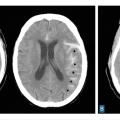

Le scanner doit être réalisé en urgence. Il montre une hyperdensité des espaces sous-arachnoïdiens, évalue la sévérité par l’échelle de Fisher et recherche les complications précoces (fig. 1 et tableau 1).